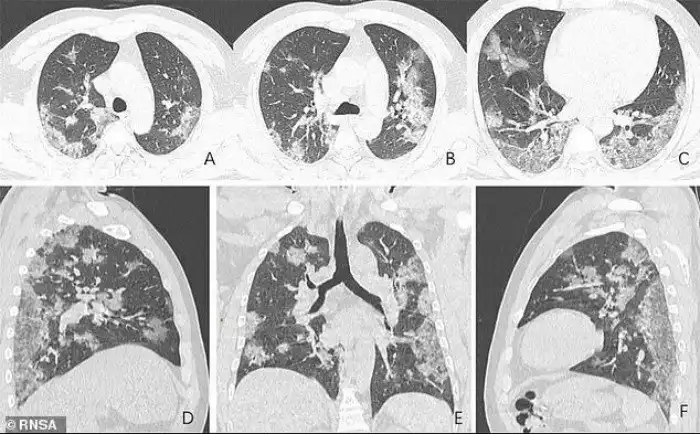

Рентгеновские снимки и томограммы легких 44-летнего пациента, умершего от коронавируса, были представлены китайскими врачами. Они дают подробную картину того, как вирус разрушает легкие человека. На снимках видны белые пятна в нижних отделах легких. Медики называют их "субплевральными уплотнениями по типу матового стекла". В этих областях воздушные пузырьки легких частично заполнены содержимым. Похожие поражения наблюдались также у пациентов с атипичной пневмонией и ближневосточным респираторным синдромом.

Умерший 44-летний мужчина из Китая жил в Ухани и работал на местном рынке морепродуктов, который, вероятно, стал источником нового вируса. Он был госпитализирован 25 декабря 2019 года после двух недель болезни. Врачи диагностировали у него пневмонию и острый респираторный дистресс синдром. Несмотря на лечение, он умер неделю спустя. Субплевральные уплотнения видны в его легких очень отчетливо. На снимках видно, как легкие со временем, от снимка А до снимка F, все сильнее заполняются жидкостью. Компьютерная томограмма легких 54-летней женщины, подхватившей коронавирус во время поездки в Ухань, показывает схожую картину.